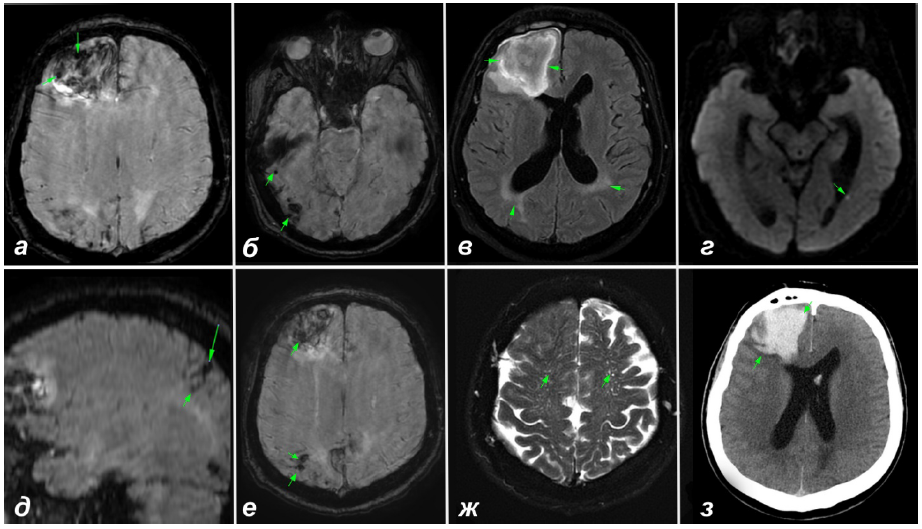

На 9-й день лечения проведена мультимодальная магнитно-резонансная томография (МРТ) головного мозга, по результатам которой выявлены проявления ЦБМС: ЦМК, КПС, задний лейкоареоз, расширение ПВП в области полуовального центра и микроинфаркты (рис. 1, а–ж).

Рис. 1. Результаты нейровизуализации пациента Ф: а – корково-подкорковая гематома в правой лобной доле, в структуре которой определяются два микрокровоизлияния, также заметны микрокровоизлияния в затылочно-теменных отделах (SWI); б – субкортикальные микрокровоизлияния в затылочно-височных отделах справа (SWI); в – задний лейкоареоз с тенденцией к распространению к полюсу затылочной доли (Fazekas 3) (FLAIR); г – микроинфаркт в левой височной доле (DWI); д – микрокровоизлияние, переходящее в корковый поверхностный сидероз (SWI); e – субкортикальные микрокровоизлияния в теменно-затылочных отделах справа (SWI), всего идентифицировано 27 микрокровоизлияний; ж – МРТ-видимые периваскулярные пространства в области полуовального центра (MacLullich 3) (Т2); з − корково-подкорковая гематома в правой лобной доле с проникновением крови в субарахноидальное пространство, край гематомы – без явных пальцевидных вдавлений (КТ)